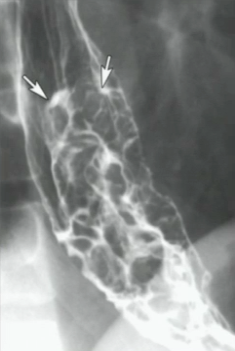

What could be causing the sign shown below?

An advanced carcinoma. Note the multiple filling defects with ulcerations.